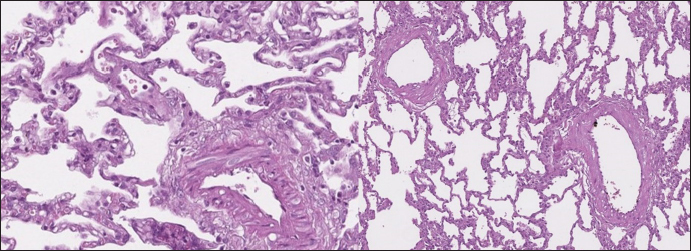

In dogs with RHF, with both Masson’s trichrome and hematoxylin and eosin staining, we found wide fields of pulmonary fibrosis, arterial thickening due to tunica media proliferation, and plexiform vascular lesions with signs of revascularization. The dog with pneumonitis showed chronic interstitial histiocytic pneumonia (Fig. 3).

In the sPCH group, we found zones of multifocal mild-to-moderate alveolar septa thickening with numerous capillary proliferation with signs of congestion. Endothelial cells were flattened, but had no signs of anisocytosis or anisokariosis. The growing capillaries expanded in pulmonary tissue, forming nodules and web-like anastomosis with bizarre vessel proliferation which affects zonal bronchi and arteriolas (Figs. 4 and 5).

Fig. 3. RHF group. Left top—aggressive lung remodeling, resembling organizing diffuse alveolar damage with collapse and fusion of the alveoli and loss of typical structure. Right top—tunica media and adventitia proliferation around pulmonary vessel. Left bottom—partial occlusion of pulmonary vessel. Right bottom—plexiform vasculopathy with lumen obstruction and revascularization, presented with onion-like structure. Stained with H&E.

Fig. 4. sPCH group. Left (dog)—portions of alveolar septae with duplicated capillaries and capillaries proliferation into arterial walls. Right (cat)—less prominent septal alteration, significant arterial walls capillary proliferation. Stained with H&E.